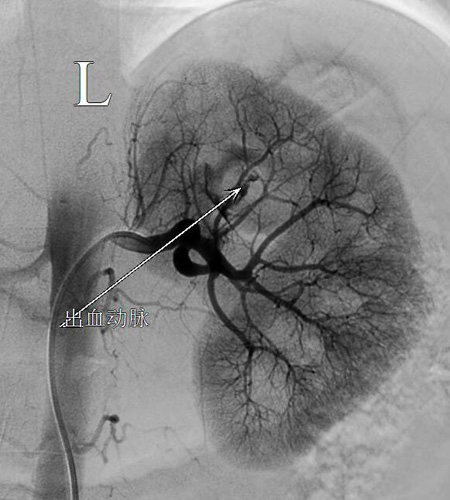

清晨6点25分,患者被送入介入手术室准备手术。当时患者神志不清,烦躁不安,引流出鲜红色血性尿。介入医学科为患者在局麻下穿刺右侧股动脉,行"左肾动脉造影+栓塞术”并栓塞止血成功。手术结束后,患者的尿色转为淡红色,转入重症医学科继续治疗。

急诊介入手术栓塞止血前后对比